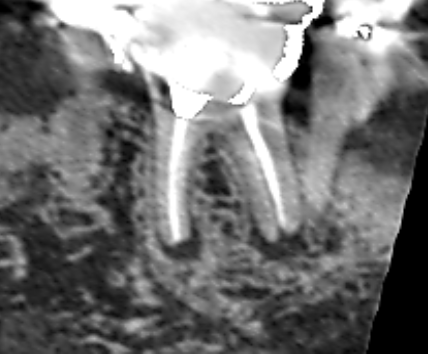

6カ月後の経過観察時のCT画像です。矢印の先にあった膿の影が消え、歯槽骨が再生しています。